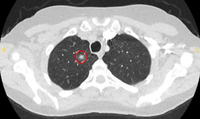

Tomografia computadorizada (TC) mostrando duas áreas (círculos vermelhos) de impactação mucoide dos brônquios subsegmentares do lobo superior esquerdo, resultando em aparência que mimetiza um nódulo

Do acervo de Dr. George Tsaknis, MD, PhD, FRCP (Londres), MRQA, MAcadMEd, PGCert; usado com permissão